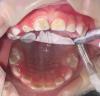

Как выбрать стоматологию для лечения кариеса у детей 2 лет

2саастаах ого кариеьын ханнык стоматологияга эмтииллэрий ? тииспит барыта кариес буолан иьэр🥲

@suderapo, 79😅у нас очень все запущено было, точнее зубы вышли без эмали🥺один зуб был на удаление, но удалось спасти

Мы младшему в отостоме пролечили, наркозтатан, иначе никак диэн, хотели сохранить передние зубы🥹